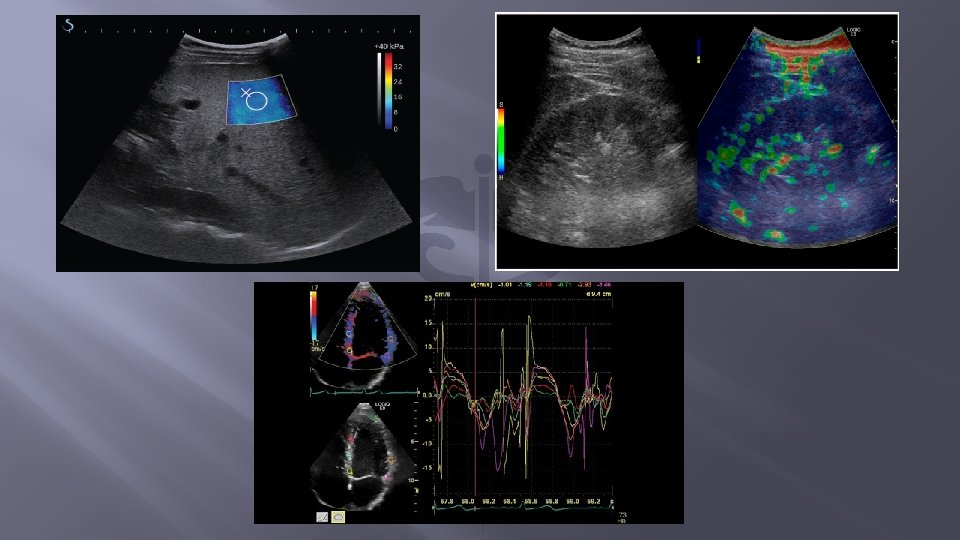

SWEI(Share Wave Elasticity Imaging) Similar cu ARFI, push-ul este produs de fascicolul de ultrasunete al transductorului, si se creaza o harta 2 D a duritatii tesutului:

Spre deosebire de ARFI, in aceasta tehnica undele sunt perpendiculare pe directia de propagare a fascicolului de ultrasunete, iar cuantificarea se realizeaza in k. Pa.

Shear wave realizata cu un echipament Supersonic gradul de fibroza este exprimat in kilopascali. (pacient cu hepatita C)

SW-realizata cu un echipament GE - se observa ca sau facut 9 determinari in doua regiuni de interes Q-box 1 si Q-box 2 calculinduse ulterior media duritatii hepatice in esantionul studiat.

Fig. (A)Shear wave in scala de gri, este realizata cu un echipament ecografic Philips, abord intercostal. Indicatorul de elasticitate arata o valoare de 3. 135 k. Pa(normal) Fig. (B)share wave a unui ficat dur calibratorul de duritate indica 8, 91 k. Pa

� � � (A) Ecografie 2 D in scala de gri evidentiaza modificarile cirotice cu ascita perihepatica. (B) Elasticitatea hepatica, are o valoare de 42. 6 k. Pa de 8 ori valoarea normala. (C) Gradientul presional, la nivel portal, este de 26. 3 mm. Hg (N=10 mm. Hg) valoare care sugereaza o hipertensiune portala severa.

SSI(Supersonic Share Imaging) � � � Una din cele mai avansate metode de elastografie ce creaza o harta 2 D, color, in timp real, a elasticitatii unui tesut. Are implementate doua inovatii: prima ar fi faptul ca foloseste simultan mai multe push-uri invecinate iar a doua, consta in viteza foarte mare de procesare a imaginii (peste 10. 000 cadre/s). Este deasemeni o metoda cantitativa, utilizata in elastografia de inalta rezolutie pentru sin, tiroida, ficat, prostata, testicol, musculoscheletal etc.

Imagine Supersonic shear-wave: � (A) - albastru inchis reprezinta tesutul hepatic normal; si � (B) - imaginea unui ficat cirotic-albastru-verzui deschis. Q-box reprezinta zona pe care s-a calculat media duritatii tesutului hepatic.